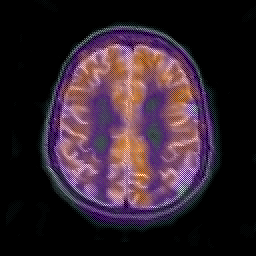

Alzheimer's disease: overlay -- Slice #18

[Home][Help][Clinical] Slice 18